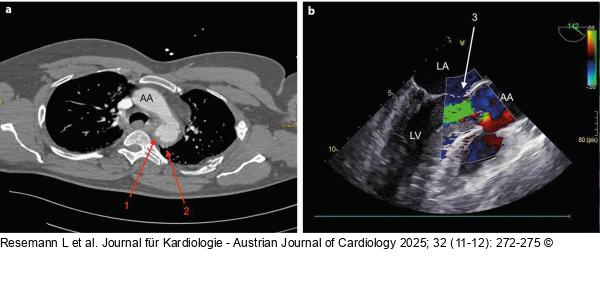

Abbildung 1: Trauma-CT 1a: Trauma-CT: AA – Aorta ascendens; 1 – Pseudoaneurysma in loco typico; 2 – beginnendes mediastinales Hämatom, 1b: TEE während TEVAR: LA – linker Vorhof; LV – linker Ventrikel; AA – Aorta ascendens; 3 – hochgradige Aortenklappeninsuffizienz |

1a: Trauma-CT: AA – Aorta ascendens; 1 – Pseudoaneurysma in loco typico; 2 – beginnendes mediastinales Hämatom, 1b: TEE während TEVAR: LA – linker Vorhof; LV – linker Ventrikel; AA – Aorta ascendens; 3 – hochgradige Aortenklappeninsuffizienz |